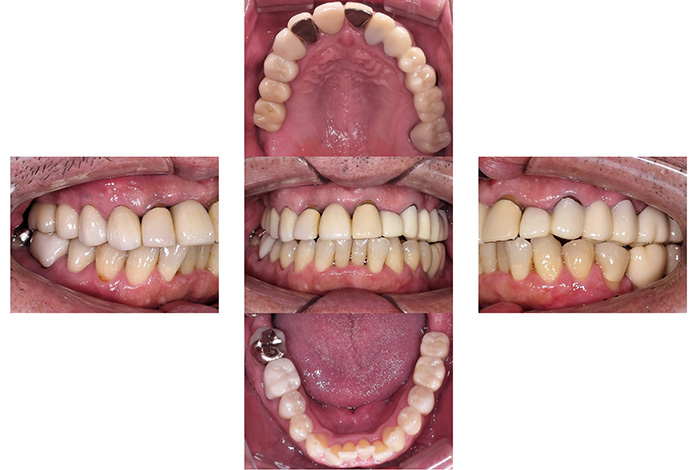

Before

After

インビザラインによる全体矯正後に補綴治療を行い、咬合と審美性を総合的に改善した症例です。

まずマウスピース型矯正装置(インビザライン)により歯列および咬合関係を整え、その後、必要部位にジルコニア補綴を行いました。

矯正のみ・補綴のみではなく、両治療を組み合わせることで機能性と審美性の両立を目指した包括的治療です。

奥歯の噛み合わせと前歯の歯並びを同時に改善した症例(インビザライン+ジルコニア)

【治療前の状態】

患者様は、奥歯でしっかり噛めないことと、前歯の歯並びの乱れを気にされ来院されました。診査の結果、前歯部の叢生(歯並びの乱れ)と、臼歯部の離開咬合(奥歯がしっかり噛み合っていない状態)が認められました。また、臼歯部には古い金属修復物が装着されており、機能面だけでなく審美面においても改善が必要な状態でした。

【治療後】

前歯の歯並びが整い、見た目の改善が認められました。また、奥歯でしっかり噛める状態となり、咬合機能の回復が得られています。

【治療のポイント】

本症例では、歯並びの改善だけでなく、噛み合わせの回復と審美性の向上を同時に行っています。当院は一般歯科と矯正治療の両方に対応しているため、矯正治療後に別の医療機関で補綴治療を行う必要がなく、一貫した治療計画のもとで治療を完結することが可能です。また、奥歯の噛み合わせを矯正治療のみで改善する場合、治療期間が長くなることがありますが、本症例では補綴治療(アンレー)を併用することで、比較的短期間で咬合の改善を行いました。さらに、古い金属修復物をジルコニアに置き換えることで、見た目の改善と機能性の両立を図っています。